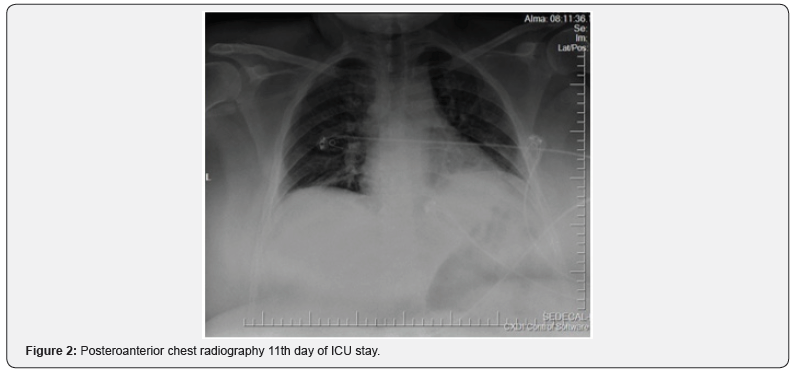

On the anteroposterior chest X-ray (Figure-1), a decrease in ventilation was observed. Intubation tube was found to be in the right main bronchus. And drawn over the carina level. Mechanical ventilator mode was SIMV-V (tidal volume 450ml, PEEP 6cm H₂O, respiratory rate 12 breaths / minute, PEEP above 8cm H₂O). Sedation (propofol 2mg / kg / h, remifentanyl 0.1 microgram / kg / min) was applied for agitation. Bronchoscopy was performed to evaluate bronchial obstruction and there was no obstruction of the respiratory tract in both lungs but, alveolar edema and bronchomalacia were observed. Viral pneumonia and ARDS were considered. Thoracic tomography revealed no sign of ground glass opacities and the diagnosis of viral pneumonia was avoided. However, PCR was sent from bronchoalveolar lavage to confirm the diagnosis. Bacterial induced ARDS was suspected. With the recommendation of infectious diseases, intraveneous 3x4.5 grams of tazobactam-piperacillin were started. Right jugular internal cannulation was performed. On the second day of her hospitalization, sedation was terminated. Patient had spontaneous breathing and followed with CPAP mode. However, oxygen saturation drops to 85% and the mechanical ventilation switch to a controlled mode. (SIMV-V, tidal volume 450ml, PEEP 6cm H₂O, PEEP above 8cm H₂O, respiratory rate 12 breaths / min). Figure 2 No pathology was recorded in the control chest x-ray. Sedation terminated on 3rd day of ICU. Hypoxia was observed after self-extubation and the patient was re-intubated. Bronchospasm episodes were observed, and viral PCR result was negative on the 3rd day of ICU stay. There was no positive growth in blood, urine, tracheal aspirate cultures after hospitalization.